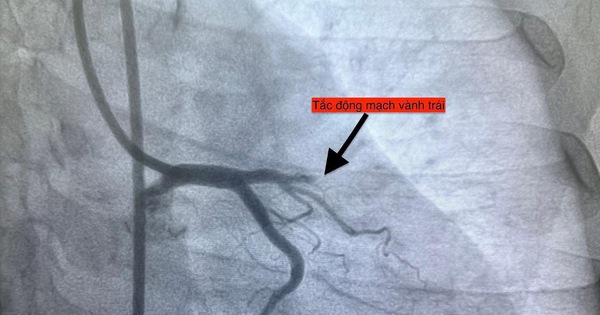

TP.HCM chuyển mùa, Bệnh viện đa khoa khu vực Thủ Đức tiếp nhận 4 ca nhồi máu cơ tim cấp trong 1 ngày. Cảnh báo nguy cơ tim mạch tăng do biến động nhiệt độ và độ ẩm